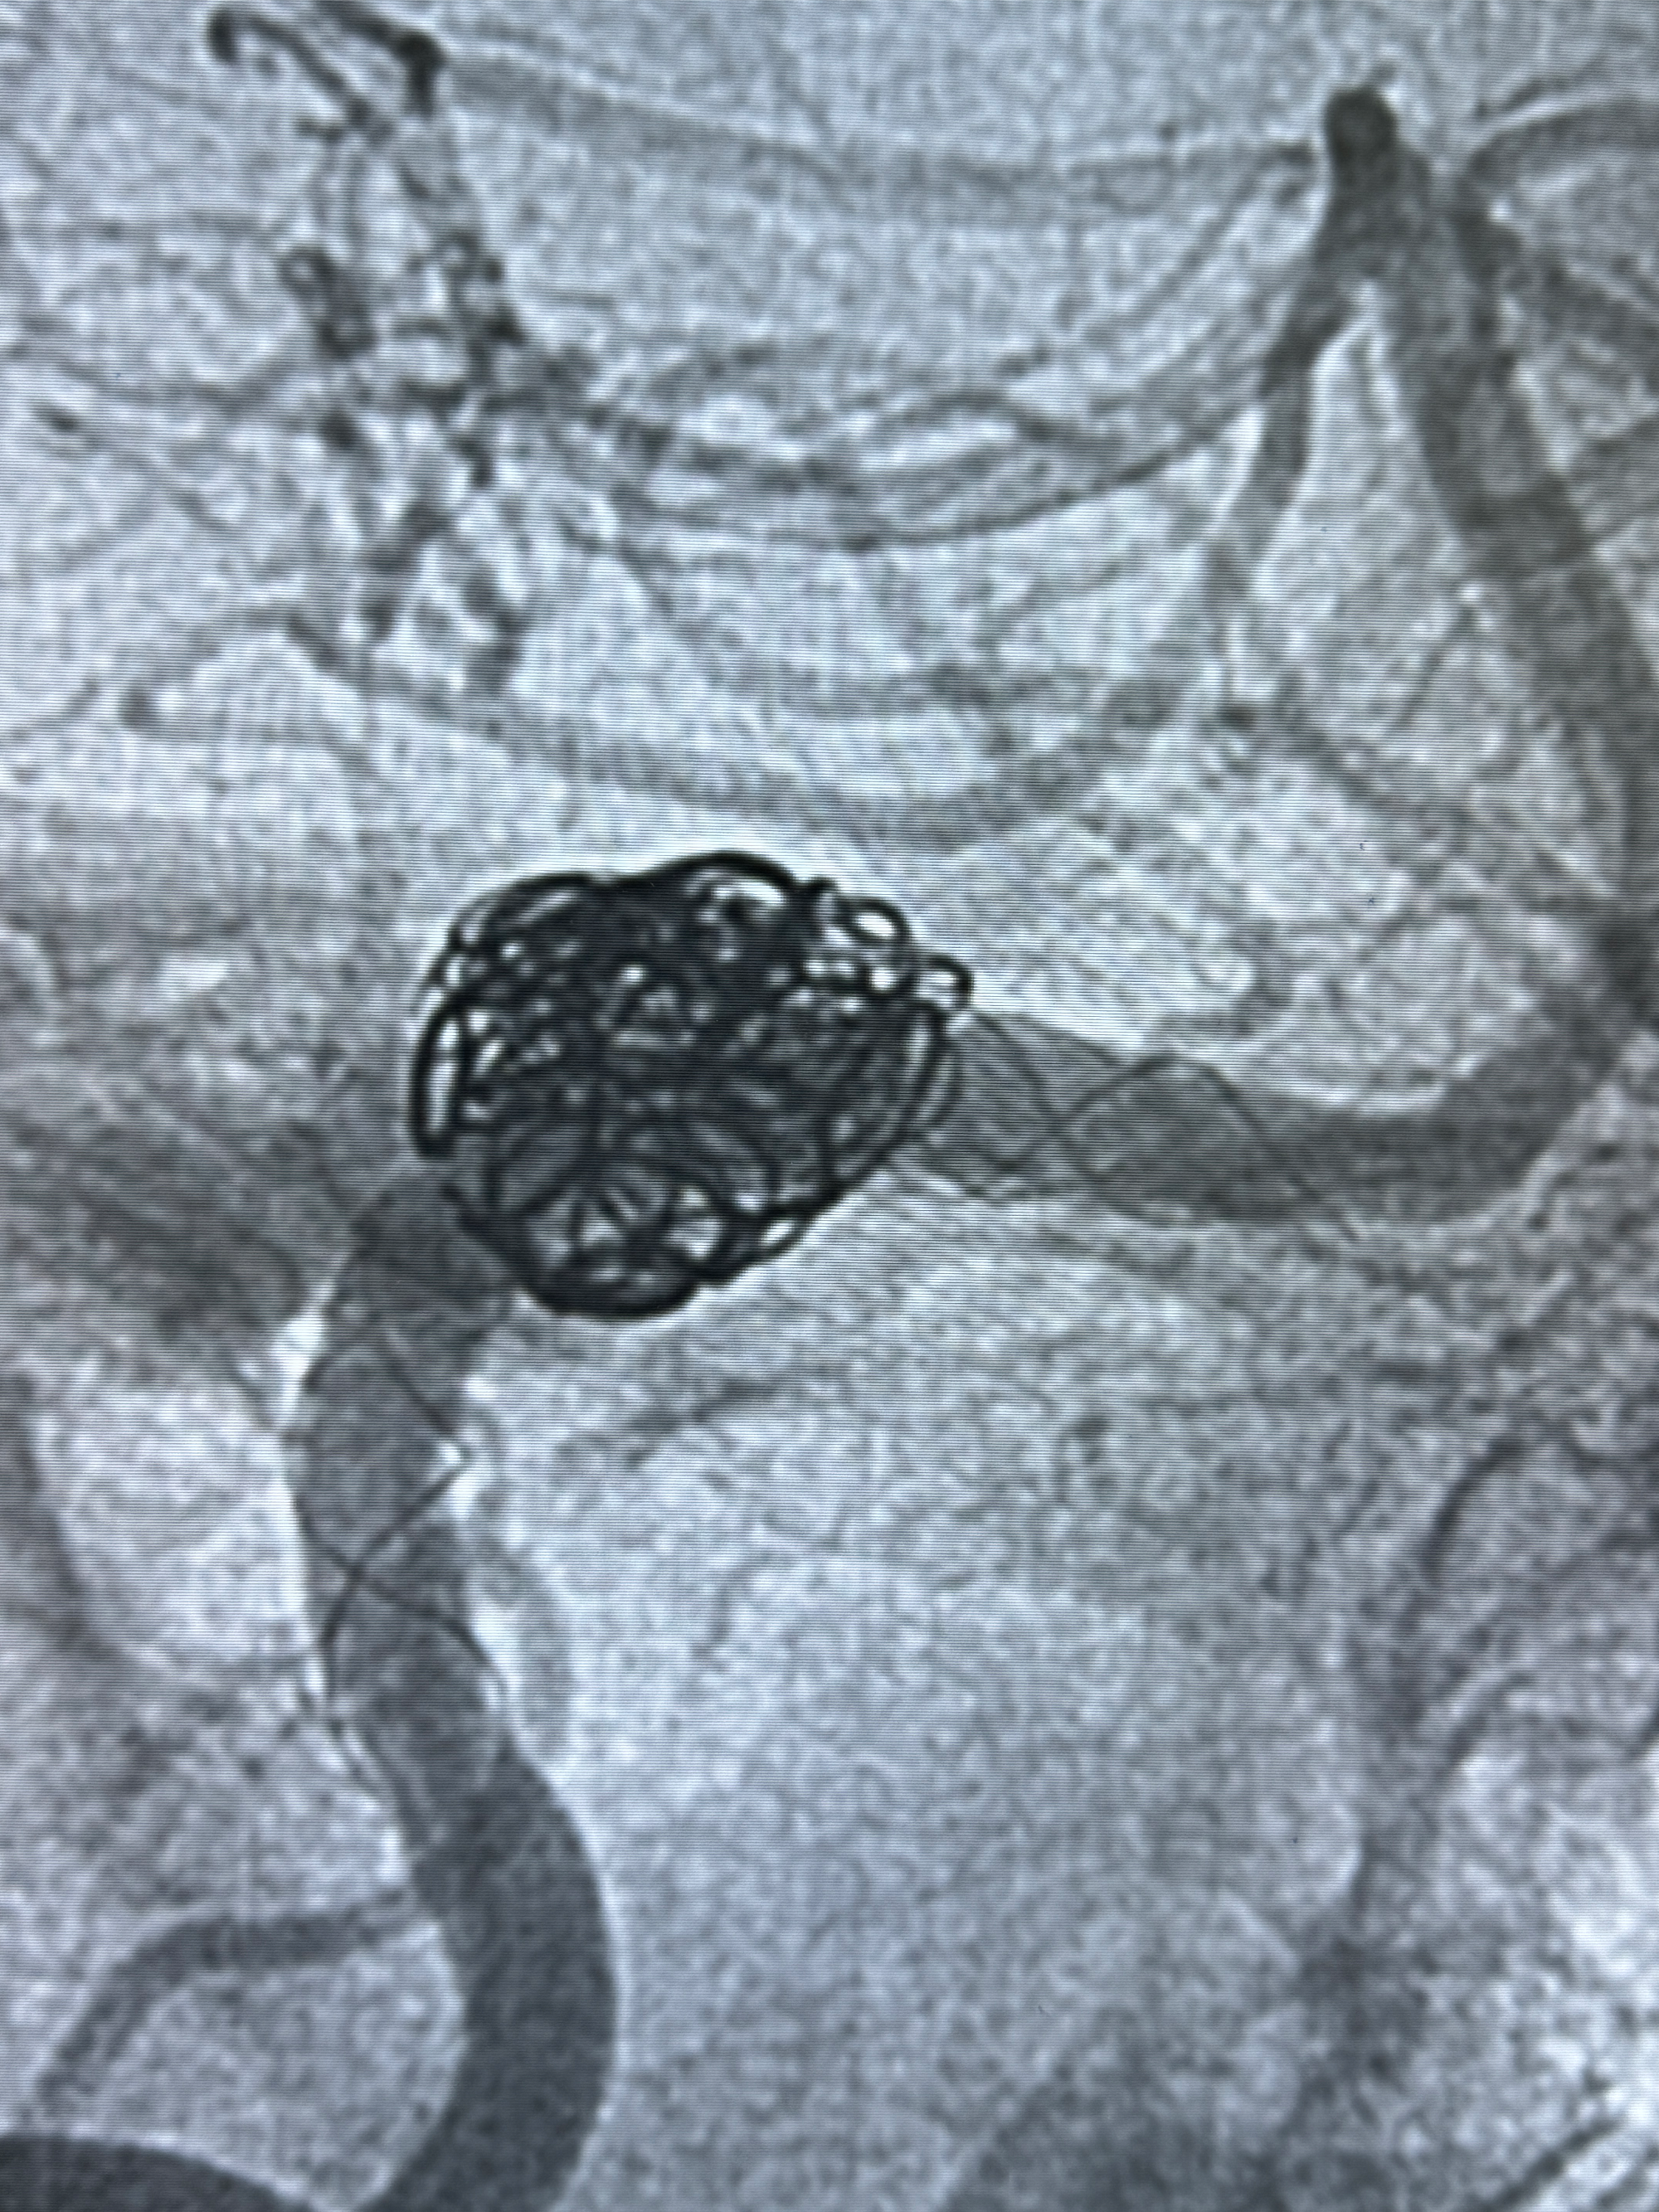

2024-01-08DSA:右侧椎动脉V4段夹层动脉瘤双支架辅助弹簧圈栓塞术后

患者支架辅助治疗后18个月,动脉瘤痊愈